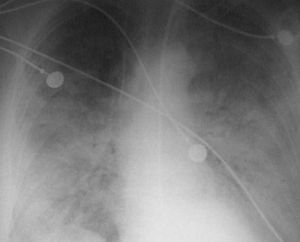

英文名:Staphylococcalaureuspneumonia為體內局部金黃色葡萄球菌感染灶經血液播散而致肺部感染。病理改變以廣泛出現血壞死多發性小膿腫為其特點。臨床表現比較嚴重,多見於1歲以內小嬰兒,在呼吸道感染和皮膚感染後突然高熱不退,年長兒持續高熱,新生兒低熱或無熱甚至體溫不升。起病急、呼吸道症狀出現早,肺炎進展迅速、皮膚花紋,有麻疹樣、猩紅樣皮疹。嘔吐、腹瀉、腹脹如鼓。患兒煩躁嗜睡,嚴重者驚厥,休克。肺部體徵出現亦早臨床症狀與胸片所見可不一致。病初臨床症狀很重,便X線徵象很少,當臨床症狀有所好轉時X線卻見有肺大泡出現;病變發展迅速,可在數小時內出現肺膿腫、肺大泡、膿胸、膿氣胸;嚴重者縱隔積氣、皮下氣腫,支氣管胸膜瘺。

X線檢查早期肺紋理增多,模糊,病程4-5日可出現大小不等片狀病灶,以兩肺下野和右上肺多見,病後6-11日病灶增多,分布較廣,互相融合,呈大片浸潤狀,但不局限於某葉,可有一側胸腔積液。